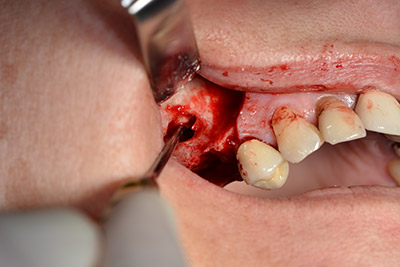

Die klassische Schnittführung (krestal, Entlastung bukkal) und das Präparieren des Mukoperiostlappens erlauben eine gute Übersicht.

In diesem Fall werden Sky Implantate (bredent) verwendet, deren chirurgisches Protokoll die Pilotbohrung mit etwa 1.200/min vorschreibt (Abb. 9).